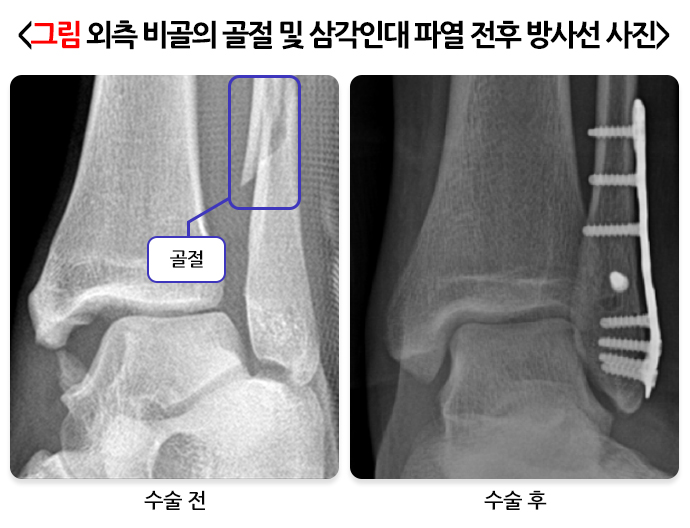

발목을 외번되는 방향으로 다치면 내측 발목 인대가 손상됩니다. 주로 공을 밟거나 상대방과 접촉해 발목에 과도한 힘이 가해지면서 다칩니다. 축구할 때는 바깥쪽에서 태클이 들어와 안쪽의 인대가 늘어나면서 발생합니다. 삼각인대는 얕은 층과 깊은 층이 있는데 깊은 층이 파열되면 발목이 매우 불안정해집니다. 또한 깊은 층 파열에는 바깥쪽 복숭아뼈(비골)의 골절이 동반되는 경우가 많습니다. 오타와룰에 따라 발목의 내측과 외측 후방이 아프면 골절 및 내측 삼각인대 파열을 의심하고, 실제 골절이 일어나 뼈 간격이 벌어졌다면 수술적 치료를 시행해야 합니다.